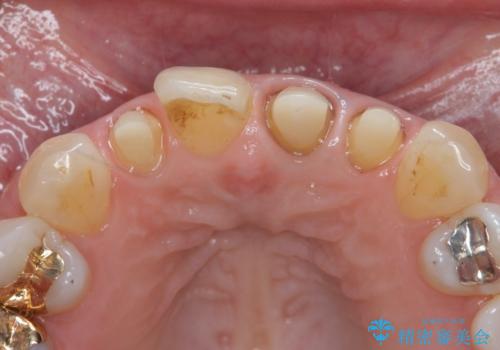

- 前歯のクラウンの歯肉の位置が年々変化し、歯ぐきのフチが黒くなってしまった、綺麗にしたいと希望されて来院されました。

装着されているセラミッククラウンを除去したのち、現在の歯ぐきのラインにしっかりと合う精度の高いオールセラミッククラウンを作製していきます。